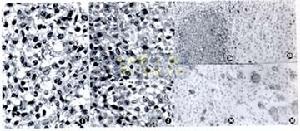

朗格罕細胞間可見明顯細胞間隙

(10)免疫組織化學染色 如前所述,近年發現郎格罕細胞具有CDla的免疫表型,以抗CDla單抗作免疫組化染色呈特異性陽性反應。此外對以下四種酶也可呈陽性反應,即S-100神經蛋白、α-D-甘露糖酶、ATP酶和花生凝集素。